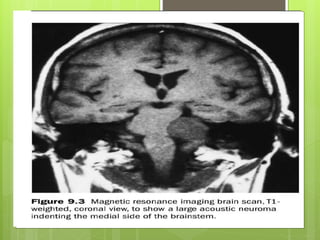

Clinical Significance

Symptoms of damage

Patients may present with pain in or behind the ear preceding

or appearing with the development of facial weakness.

 Damage to the vestibulocochlear nerve may cause the

following symptoms:

 hearing loss

 vertigo

 false sense of motion

 loss of equilibrium (in dark places)

 nystagmus is a condition of involuntary (or voluntary, in

some cases) eye movement

 motion sickness

 gaze-evoked tinnitus -is the perception of sound)